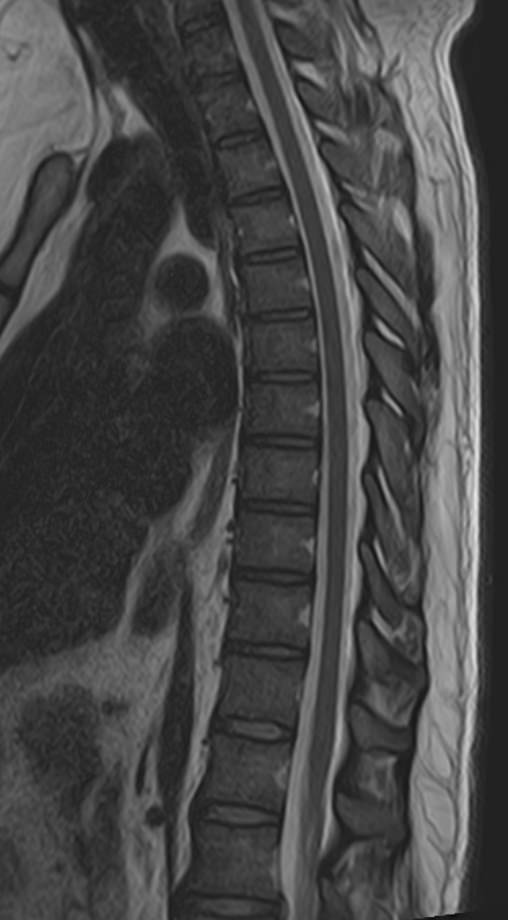

В клинике «Доступная медицина» проводится комплексное обследование позвоночника, включающее два протокола сканирования — МРТ грудного и поясничного отдела.

Магнитно-резонансная томография является наиболее точным и эффективным способом диагностики различной патологии позвоночного столба. Метод позволяет визуализировать не только костные структуры позвонков, но и оценивать состояние спинного мозга на исследуемом уровне, нервных корешков, связочного аппарата и окружающих мягких тканей. МРТ сочетает в себе высокую точность и информативность, при этом является безболезненной, неинвазивной и безопасной процедурой, так как во время исследования не применяется вредное рентгеновское излучение. В основе метода лежит использование магнитного поля, которое не оказывает негативного действия на организм человека.

Комплексное обследование грудного и поясничного отдела позвоночника обычно требуется в тех случаях, когда имеется подозрение на множественное поражение позвоночного столба, которые могут быть вызваны опухолевыми, воспалительными или дегенеративными заболеваниями позвоночника.

Магнитно-резонансная томография, предусматривающая обследование средней и нижней части спины, охватывает область семнадцати позвонков: двенадцать из них формируют заднюю стенку грудной клетки, пять находятся между ребрами и крестцовым отделом. Исследование позволяет визуализировать:

МРТ грудо-поясничного отдела позвоночника обладает высокой чувствительностью и специфичностью. Она позволяет не только определять границы патологических очагов, но и решает более сложные диагностические задачи. МР-сканирование является обоснованным методом выбора при врожденных аномалиях развития, синдроме фасеточных суставов, межпозвонковых грыжах, остеомиелите, заболеваниях спинного мозга, вертебральных опухолях.